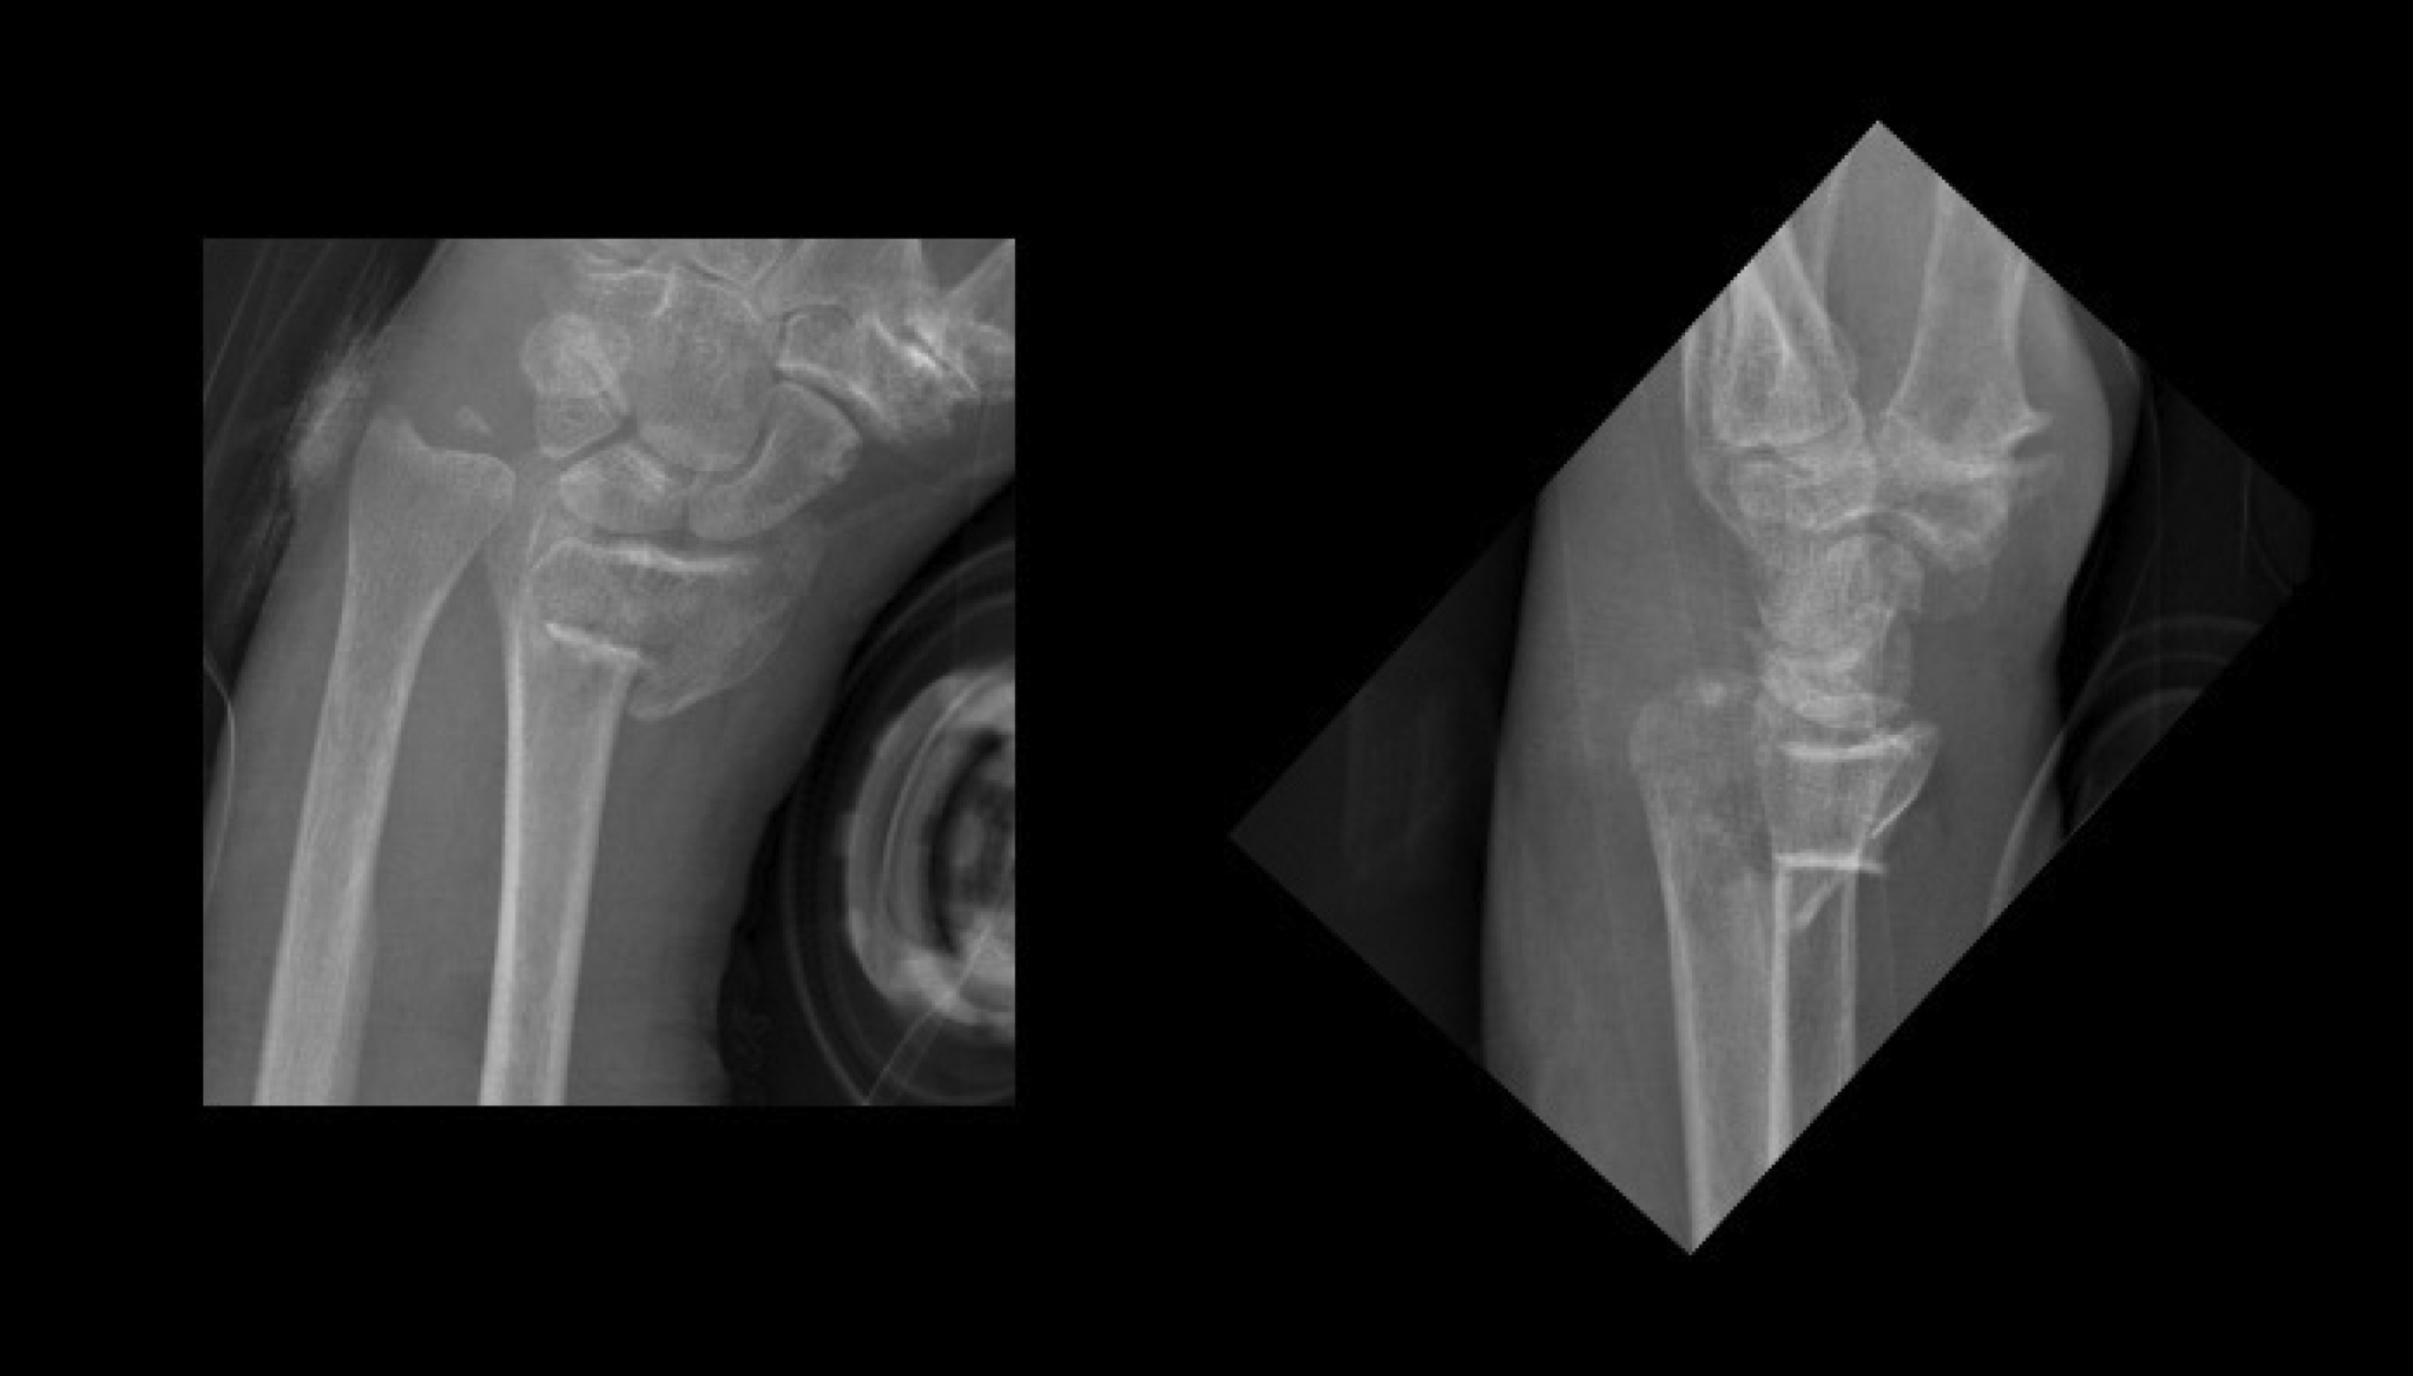

A 72-year-old woman who fell directly on her left arm sustained an open DRF with an anterior displacement. How can this DRF best be classified? And based on biomechanical principles of DRFs, which type and configuration of osteosynthesis would be most adequate for this osteopenic fracture? ( Fig. 1 )

Fig. 1, Open comminuted articular DRF.